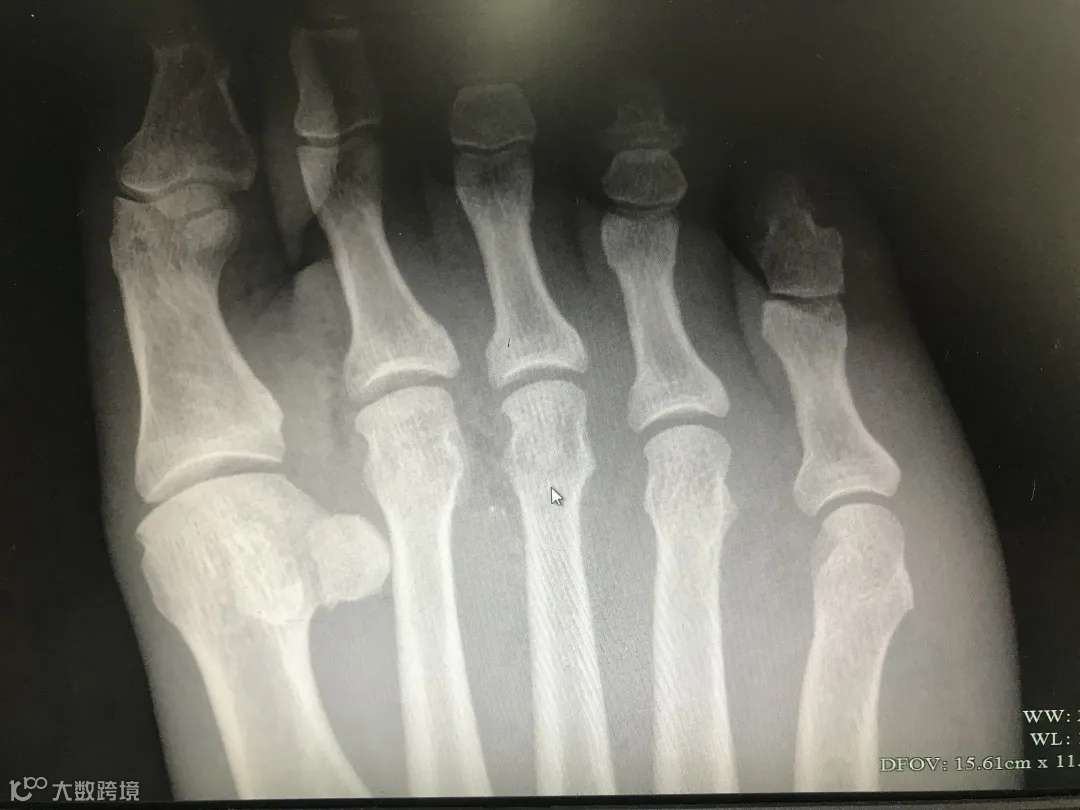

12月22日晚,女演员杨谨华在社交媒体分享近日生活,其中提到自己在家被木头直插脚底,被朋友抓去急诊室处理,还感谢医生在没有划开脚底的情况下挑出了木屑。

“有天晚上拍戏收工后,在家被木头直插我的脚底,隔天一早本想先去拍戏,拍完再去处理,最后还是被同事抓着去急诊处理,想到脚底要打麻药还有可能割一刀,就开始流汗,最后医生坚持不割一刀的情况下,挑出了细小的木屑”。

足部伤口虽小,也要注意

生活中,不少朋友因赤脚或意外,导致足部被扎伤,往往贴张创口贴,毫不在乎,但实际上,即使是小伤口,也有造成严重后果的可能。

另外,如果被生锈的钉子扎伤,可能会导致破伤风感染,需要到正规医院进行治疗,必要时注射破伤风疫苗或破伤风针。

建议大家在日常生活中加强防护,尽量不要光脚,遭遇扎伤、刺伤、擦伤,一旦发现异常情况,一定要及时到正规专科医生处进行治疗。

同时,也要特别提醒老人及其家属,由于老人脚底血供较差,异物扎伤后表皮伤口不大、出血量不多,更易忽视,如出现扎伤等情况,一定要及时就医,以免出现不良后果。